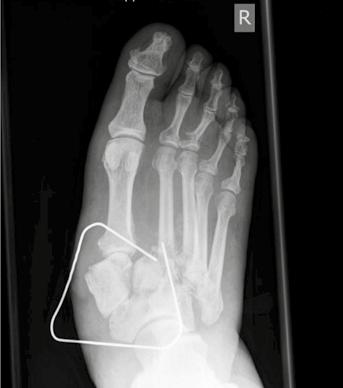

Die Charcot-Arthropathie bzw. neuropathische Osteoarthropathie (NOAP) des Fußes und Sprunggelenkes ist eine schwerwiegende Form des Diabetischen Fußsyndroms. Es ist ein deformierender und zerstörerischer Prozess auf dem Boden einer Polyneuropathie, der zu gravierenden Instabilitäten, rezidivierenden Ulzera und bakteriellen Superinfektionen führen kann (Abb. 1). Schlussendlich kann dieses Erkrankungsbild bis zur Amputation führen. Ziel der Behandlung des Charcot-Fußes ist es daher, eine Amputation zu verhindern. Dies gilt vor allem für die Majoramputation, da dieser Eingriff insbesondere beim diabetischen Patienten statistisch signifikant mit erhöhter Morbidität und Mortalität einhergeht 123.

Zur topographischen, rein radiologischen Einteilung nach Befallsmuster wird meist die Klassifikation nach Sanders u. Frykberg verwendet. In Anlehnung an die Unterteilung von Sanders wird die diabetisch-neuropathische Osteoarthropathie in fünf Haupttypen klassifiziert, die den Hauptprädilektionsstellen der Erkrankung am Fuße entsprechen. Dabei wird die Häufigkeit für den Befall von Sanders & Frykberg wie folgt angegeben: Typ I = 15 % ‚Typ II = 40 % , Typ III = 30 % , Typ IV = 10 % und Typ V = 5 %. Koller ermittelte ähnliche Ergebnisse in seiner Studie 20. Die häufigsten Veränderungen am Fuß der diabetisch-neuropathischen Osteoarthropathie entfallen somit auf die Typen I, II und III (ca. 80 %). Nicht selten zeigt sich ein kombiniertes Befallsmuster (Abb. 2) 21.

- Typ I: Beim Typ I findet man Knochennekrosen im Bereich der Metatarsophalangealgelenke. Diese Nekrosen können zur sogenannten „candy stick deformity“ („Zuckerstängel-Deformität“) des Knochens führen, mit der Gefahr der knöchernen Durchspießung der Fußsohlenhaut.

- Typ II: Typ II betrifft die Tarsometatarsalgelenke, also den Bereich des Lisfranc-Gelenks, und hat als wesentliche Konsequenz – wie beim Typ III – den Verlust der Rückfußstatik zur Folge. Es kommt häufig zur Ausbildung eines Knick-Plattfußes mit deutlicher Vorfußabduktion.

- Typ III: Beim Typ III der DNOAP ist die Nekrose hauptsächlich auf den Bereich des Chopart-Gelenks, den Bereich zwischen Talus und Os naviculare, begrenzt. Hier entwickelt sich der klassische Tintenlöscherfuß mit völligem Einbrechen des Längsgewölbes und Drucküberlastung in der Mitte der Fußsohle.

- Typ IV: Bei diesem Typ, der zu den selteneren Verlaufsformen zählt, zeigt sich die Veränderung im Bereich des oberen Sprunggelenks (OSG). Es kommt dabei häufig zu massiven Instabilitäten.

- Typ V: Diese seltene Verlaufsform der DNOAP betrifft den Calcaneus und das dazugehörige talocalcaneare Gelenk. Es führt zum Zusammenbrechen dieses Gelenkabschnittes mit der zwangsläufigen Verplumpung des gesamten Rückfußes oder zu Schnabelfrakturen des Calcaneus, bedingt durch den Zug der Achillessehne.